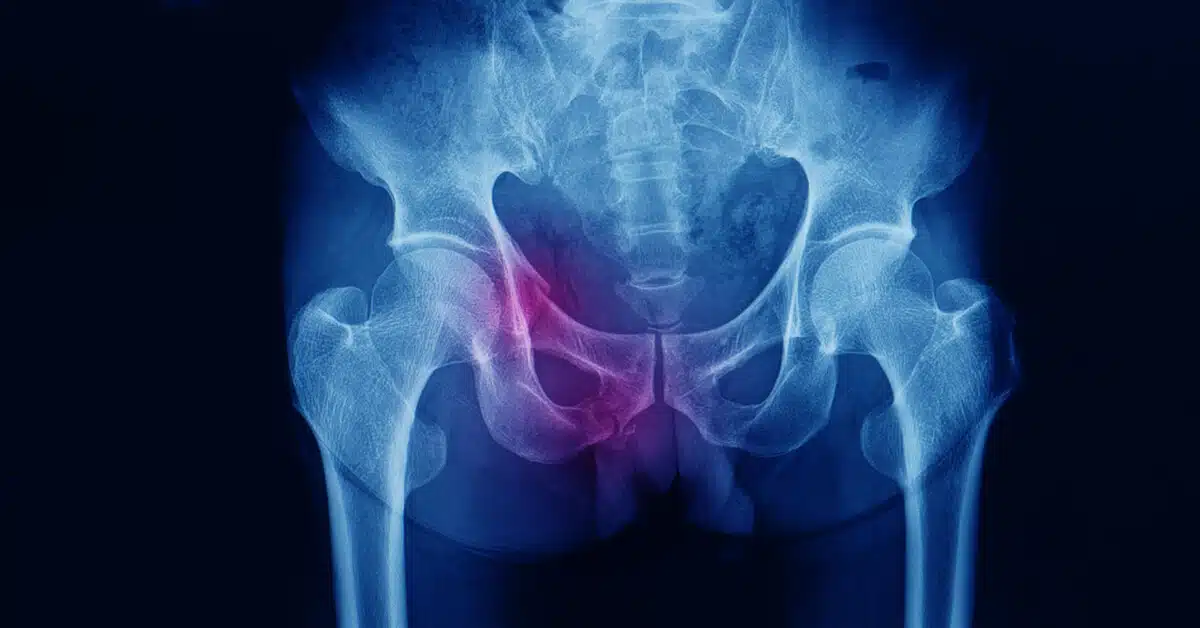

كسر الحوض هي أحد الإصابات التي قد تتعرض لها عظام الحوض والتي تربط بين عظام العمود الفقري ومنطقة الوركين والساقين، ويحدث ذلك الكسر في حالة التعرض لضربة قوية أو حادث شديد، وتظهر أعراضه بشكل تدرجي حيث يشعر المريض بألم وتورم في المنطقة ثم يزداد الأمر سوءًا بشعور بحركة في مفصل الحوض أو ظهور تشوهات في العظام، ويجب على المريض استشارة الطبيب من أجل الخضوع للتشخيص الدقيق وتحديد العلاج المناسب لكسر الحوض.